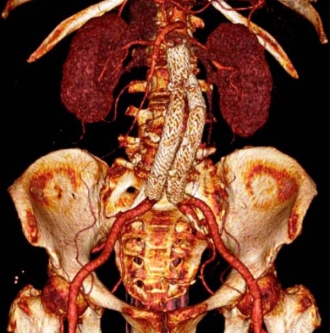

手術前(7cm腹部大動脈瘤)